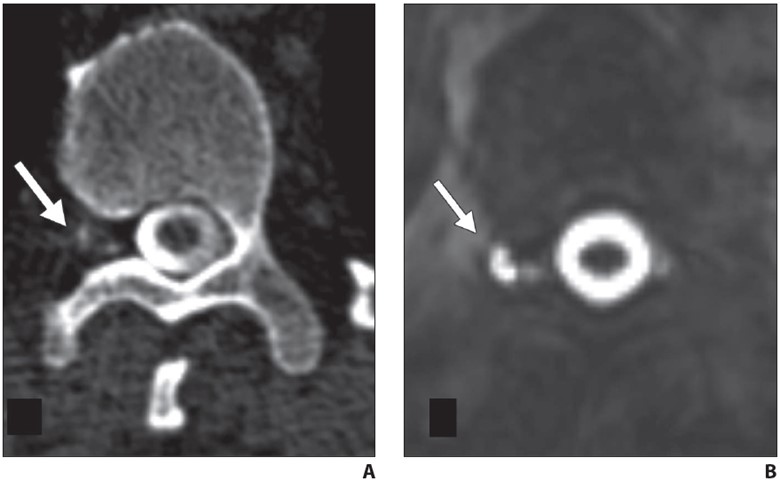

Once whole spine CT is initiated, at least two whole spine acquisitions phases should be performed in succession to maximize temporal resolution. Multiphase acquisition allows scrutinization of paraspinal densities over time, as CVF often fills transiently on a single phase of acquisition (Fig. 4).

Fig. 4—62-year-old woman with orthostatic headache.

A, Axial early phase image of right lateral decubitus pressure-augmented dynamic CT myelogram shows filling of small paraspinal vein (arrow) lateral to perineural cyst at T11–12 level.

B, Delayed-phase MR image shows contrast material dissipated from vein (arrow), consistent with CSF venous fistula.

Side-by-side comparison of dynamic CT images with preprocedural 3D heavily T2-weighted fat-saturated spine MRI helps distinguish partial filling of perineural cysts from CVF (Fig. 5).

Fig. 5—42-year-old man with orthostatic headaches.

A, Axial decubitus dynamic CT myelogram shows irregular contrast enhancement in right T12-L1 neural foramen (arrow).

B, Axial heavily T2-weighted fat-saturated 3D MR image with CSF leak protocol at same level delineates irregular perineural cyst (arrow), confirming contrast pattern seen in A reflects partial filling of distal portion of perineural cyst rather than CSF venous fistula.